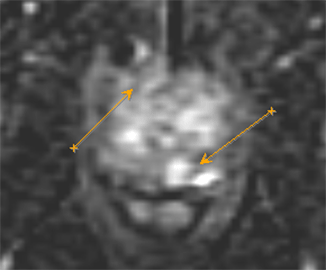

Существующие стандартные методы диагностики злокачественных опухолей предстательной железы обладают высокой точностью при выявлении заболевания. В РНПЦ ОМР им.Н.Н.Александрова используются и новые методы исследования, позволяющие улучшить стандартный подход на основе применения трансректального ультразвукового исследования с эластографией сдвиговой волны, которая открыла новые возможности количественной оценки жесткости ткани и позволяет определить локализацию подозрительных очагов.

Для подтверждения или исключения наличия злокачественной опухоли предстательной железы выполняется биопсия под контролем трансректального ультразвукового исследования. Она состоит из целевого этапа получения материала из подозрительных очагов, которые выявлены при помощи мультипараметрической МРТ таза и трансректального УЗИ с эластографией сдвиговой волны (т.к. точность определения диагноза возрастает, когда биопсия ориентирована на более жесткие области) и рекомендуется в сочетании с систематическим многоточечным этапом по определенной схеме.

Эластография показывает преимущества при выявлении в области верхушки и средней части простаты, тогда как МРТ – в визуализации базальной и переходной зон.

На рисунке представлен клинический пример пациента с повышенным уровнем ПСА. Ему выполнены мультипараметическая МРТ и трансректальное УЗИ с эластографией сдвиговой волны по данным которых определялись подозрительные очаги (указано стрелками или красным цветом). В последующем выполнена биопсии предстательной железы, которая состояла из систематического и целевого этапов. По результатам биопсии установлен диагноз рак предстательной железы с суммой баллов Глисона 4+3 (ISUP Grade 3). Пациенту выполнена радикальная простатэктомия в результатах которой подтвердилась правильно установленная стадия и лечение проведено успешно.

Установившийся тренд на изменение подходов к методике выполнения биопсии предстательной железы с включением целевого этапа при проведении систематической биопсии является результатом определенных успехов развития методов лучевой диагностики, в частности совместного использования при планировании биопсии результатов мультипараметрической МРТ и трансректального УЗИ с эластографией сдвиговой волны.